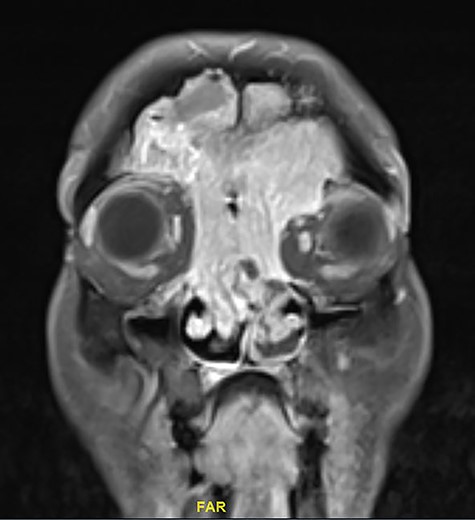

Magnetic resonance image (MRI) scanning also demonstrated a mass lesion involving both frontal and ethmoid sinuses, more into left FS causing expansion and rarefaction of the sinus wall, as well as extension of superior wall of left with extracoronal component causing mild proptosis. The lesion showed intermediate T2 signals with areas of high T2 signal along with postcontrast enhancement. No intracranial extension noticed (Figs 2 and 3).

Coronal MRI of paranasal sinuses, T1-weighted image post contrast.